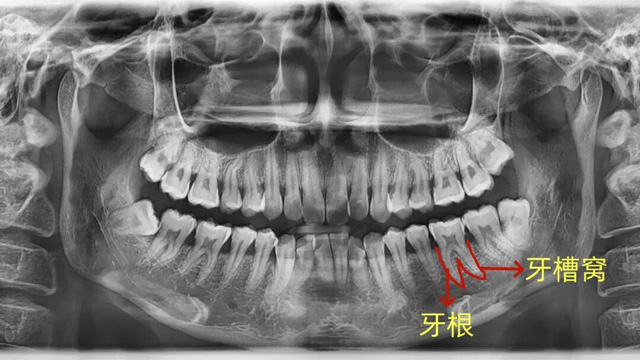

牙槽骨:牙齿的“土壤”

我们的牙根就像大树的根,深深扎根在牙槽骨里,每颗牙都有自己独立的“坑位”(牙槽窝),这是牙齿最核心的支撑。

牙周膜:牙齿的“减震器”

在牙根和牙槽骨之间,有一层充满弹性和韧性的薄膜,叫牙周膜。它既能固定牙根,又能缓冲我们咀嚼时的冲击力,保护牙齿和牙槽骨不受损伤。